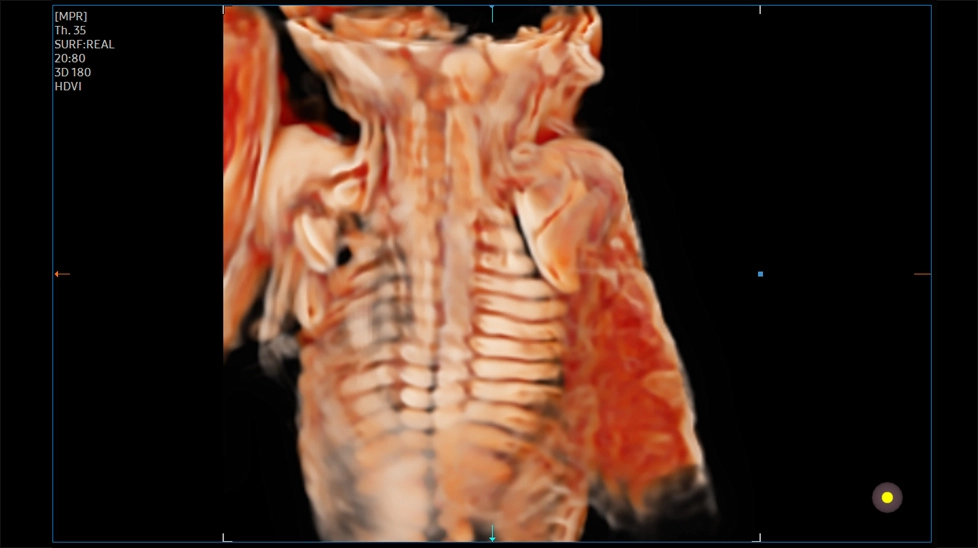

- HDVI (High Definition Volume Imaging) - повышение четкости изображения границ тканей с разной эхо-плотностью в объемном изображении (диагностика тонких повреждений тканей, дефектов мозга плода, стенок и клапанов сердца плода).

Ребра и лопатка плода с CrystalVue

Позвоночник плода с CrystalVue